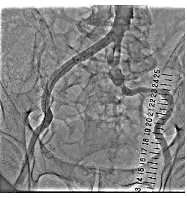

経皮的腎動脈形成術の一例

- 【1】術前

-

- 【2】ステント留置

- 【3】術後